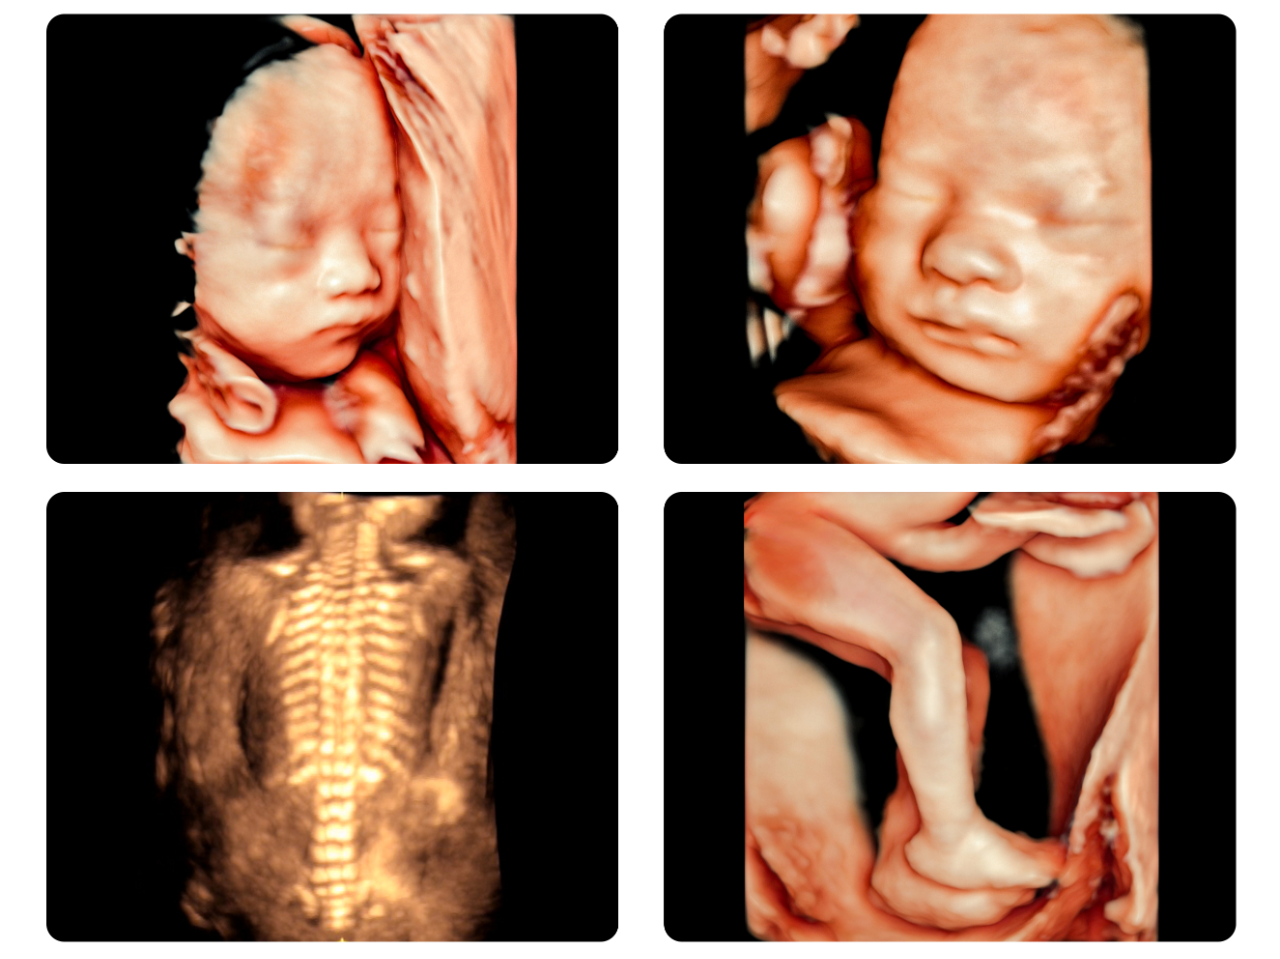

△美国GE高清四维彩超实机拍摄△

美国原装进口GE超声设备

360度全视角高清呈现 筛查更科学

瑞博医院引进的美国GE-E8高清和GE-E10超高清超声设备,超越了传统超声的限制,通过细致的多切面成像分析胎儿的解剖结构及发育状况,检查范围更广、成像更清晰、筛查更精准、评估更科学、诊断更全面。清晰观察胎儿生长发育情况,完整获取临床超声诊断医学信息,为围产医生诊断胎儿发育情况提供更为准确的监测数据。